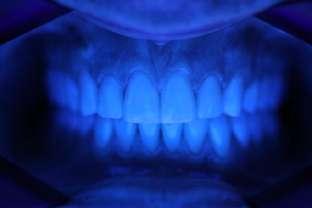

Si presenta alla nostra attenzione un paziente maschio, 35 anni, in apparente salute sistemica, fumatore, con la richiesta di controllare delle white spots, una leggera sensibilità e la richiesta di migliorare la luminosità del suo sorriso. Viene compilato e firmato il consenso informato. Il paziente viene motivato ad più efficace controllo del biofilm batterico e attraverso la condivisione dell’immagine clinica della topografia del biofilm batterico, (T.B.M.) scegliamo lo scovolino in gomma GUM Soft-picks (Sunstar) e lo sollecitiamo all’uso efficace degli spazi sovracrestali e allo spazzolamento in maniera delicata ma efficace della lingua. Sottoponiamo il paziente alla terapia parodontale non chirurgica con ablatore Comby touch (MECTRON) in modalità soft-mode per contenere la sua sensibilità. Valutiamo la sensibilità e modifichiamo i suoi stili di vita di igiene orale, di igiene alimentare e chiediamo di smettere di fumare. Il paziente riferisce di non essere disposto a rinunciare al fumo e chiediamo di ridurre il rischio di patologie e di discromie

da tabagismo passando all’uso dei dispositivi a tabacco riscaldato. Successivamente rileviamo il colore, con spettrofotometro, e con scala-colori Vita e documentiamo fotograficamente la condizione clinica presente.

Il colore rilevato è A2. Sottoponiamo il paziente ad uno sbiancamento pro-

fessionale con un principio attivo PAP (acido ftalimidoperossicaproico) che presenta il vantaggio di non sollecitare la sensibilità, pur mantenendo l’aspettativa di un risultato efficace nell’ottenere la luminosità del sorriso. Lo sbiancante ad uso professionale BRILLIANT LUMINA (Coltene), risulta essere per l’operatore di facile applicazione: ven-

gono protette le gengive con la diga liquida fotopolimerizzata, e si mescola il gel sbiancante lasciando cadere nel vasetto contenente 2 ml di gel, 3 gocce di liquido attivatore. Si ottiene il gel sbiancante di una consistenza ideale per una applicazione sulle superfici dentali sicura e pratica durante l’apposizione. Vengono eseguiti 4 step da 15 minuti.

Dopo ogni step viene aspirato il gel, pulite le superfici dentali con del cotone idrofilo e si riappone nuovamente il gel. Al termine dei 4 step, si aspira, si asciuga e viene tolta la diga. Si rileva e si condivide con il paziente il risultato ottenuto, A1, e viene documentato fotograficamente. Il paziente appare gioioso del risultato è favorevolmente colpito di non aver sofferto durante il trattamento di sensibilità. Alla persona assistita sono stati programmati dei follow-up per il trattamento successivo delle white spots con applicazioni di resine infiltranti e rigenerazione guidata dello smalto.